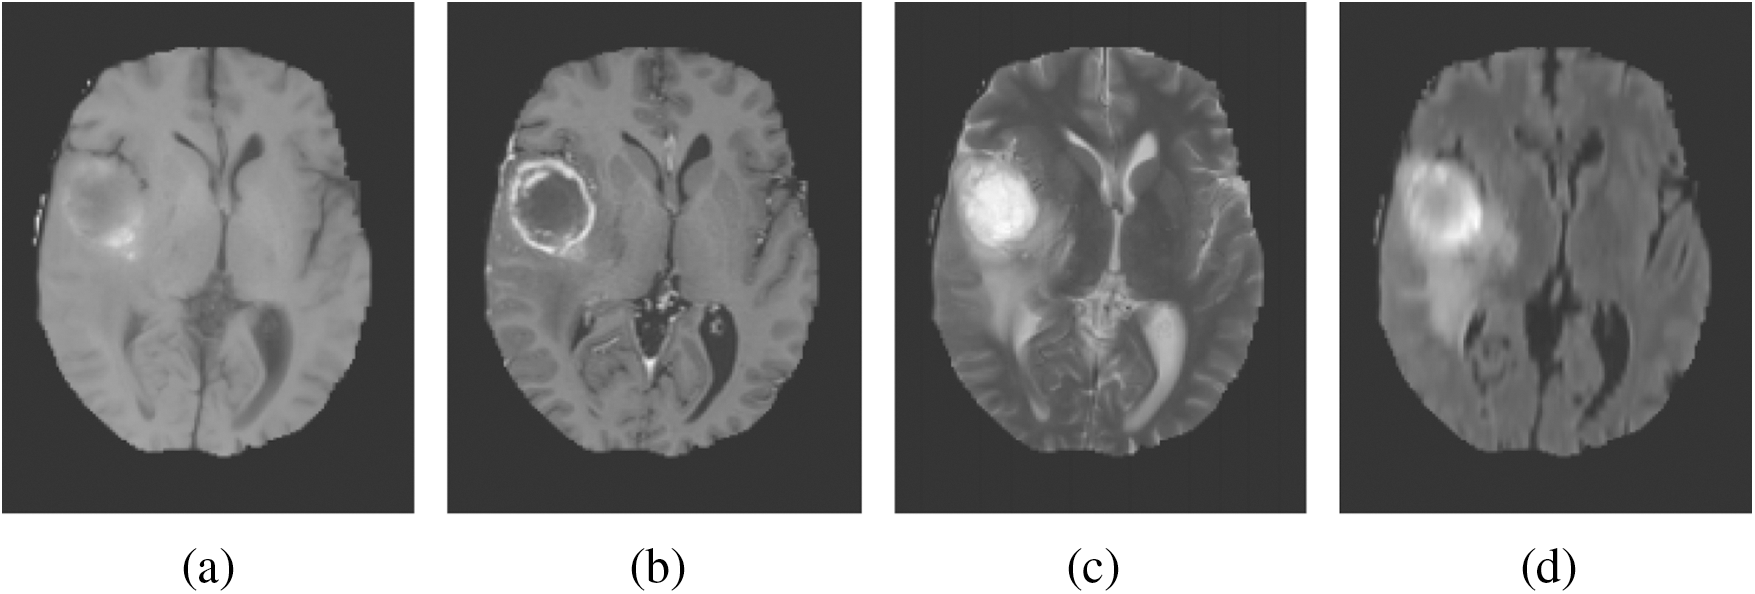

MRI depends on a multi-parameter image model that constructs different image parameters and carries more data. Fig. 1 shows the images of the brain, MRI with tumours, and the images that were obtained from four modalities: T1, T1c, T2, and FLAIR. FLAIR modalities are generally employed in the identification of expanded tumours and edemas. The most accurate portioning of BT obtained from MRI reveals an important and promising event in the diagnosis and preparation processes for further treatment. Image segmentation is an attentive action in the medical imaging process that contains a filtering process from one or more areas, which altogether forms the targeted interest. Different types of techniques have been designed in the survey to diagnose the disease integrated with threshold-based methods [6,7], region-based methods, deformable methods, classification methods, and deep learning. BT segmentation is a process of filtering the tumour area from an unaffected region which could be easily detected. Therefore accurate and efficient segmentation of tumours has been always a challenging operation due to their different sizes and locations.

Figure 1: Sample BT images. (a) T1. (b) T1c. (c) T2. (d) FLAIR